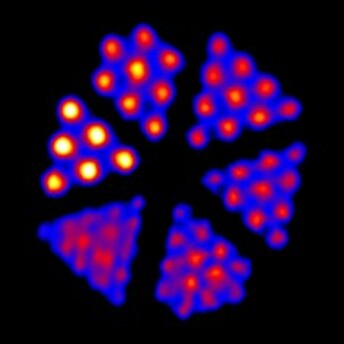

Derenzo模體的示例圖像,包括在Bruker BioSpin MRI系統(tǒng)上成像的1.0 mm至1.5 mm模式Derenzo(上)和在Inveon PET / CT系統(tǒng)上成像的F-18成像的0.7 mm至1.5 mm模體(下)